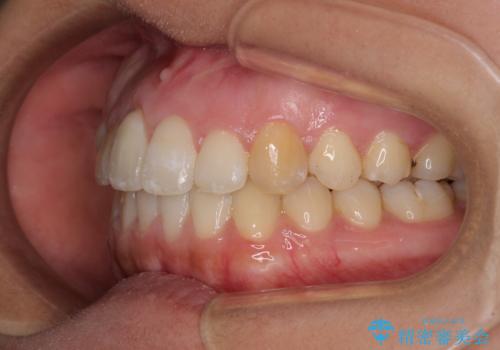

- 上下のデコボコを改善したいとのことで来院された患者様です。

近々妊娠する予定であり、極力短期間で治療したいとのことで、ワイヤー装置による非抜歯矯正治療を行うこととしました。

治療開始後すぐに妊娠され、つわりと闘いながらの矯正治療となりました。

上下顎でゴムかけを行ったのですが、早く終わらすためにしっかりと装着していただき、無事出産前に装置を外すことができました。